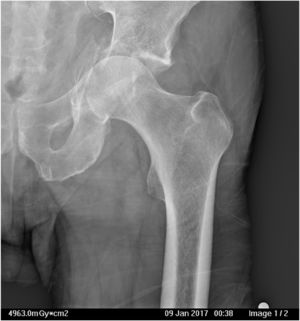

The most frequent injuries encountered were acetabular roof collapse (Fig. 1), fracture of the quadrilateral lamina with central protrusion of the femoral head (Fig. 2), and fracture of the femoral head (Fig. 1).

Initial diagnosis of the fracture was by plain X-ray in anteroposterior, alar oblique, and obturator view, and CT scan. The clinical and socio-demographic characteristics of the patients were collected: sex, age, anaesthetic risk (ASA), mechanism of production, laterality, blood test data on admission and 24 h after surgery, and type of fracture according to the Judet Letournel classification.23